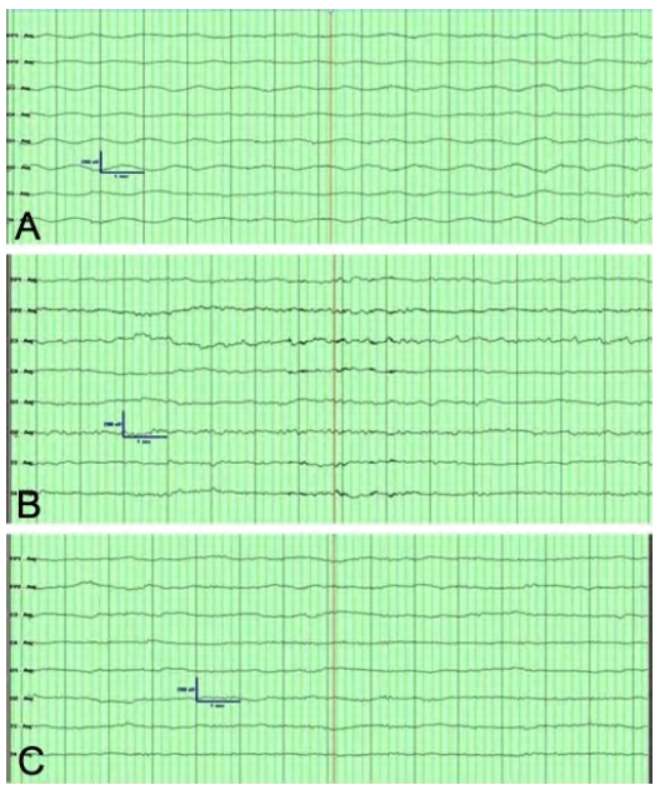

图1 脑出血

昏迷患者从昏迷初期到意识好转的脑电图A. 昏迷初期(GCS评分3分),全导以间断性0.5~1 Hz、70 μV的δ波及复合波为主,未见明显α节律;B. 昏迷后至意识好转前期(GCS评分提升至6分),O2导联可见7.5~7.9 Hz、40 μV的频段波,呈节律性出现,其它导联可见以4~7 Hz、50 μV的欠规则的θ波为主,未见明显节律性的α波及δ波;C. 意识好转期(GCS评分提升至11分),C4、O2导联可见少量的8 Hz、30 μV的α波,可见低-中波幅的β波及θ波

脑电图可分三个阶段:第一阶段为昏迷初期(GCS评分为3分),呈昏迷状态,全导以间断性0.5~1 Hz、70 μV的δ波及复合波为主,未见明显α节律;第二阶段为昏迷后至意识好转前期(GCS评分提升至6分),偶有睁眼、刺激后肢体运动,O2导联可见7.5~7.9 Hz、40 μV的频段波,呈节律性出现,其它导联可见以4~7 Hz、50 μV的欠规则的θ波为主,未见明显节律性的α波及δ波;第三阶段为意识好转期(GCS评分提升至11分),可自主睁闭眼、配合运动,C4、O2导联可见少量的8 Hz、30 μV的α波,可见低-中波幅的β波及θ波。